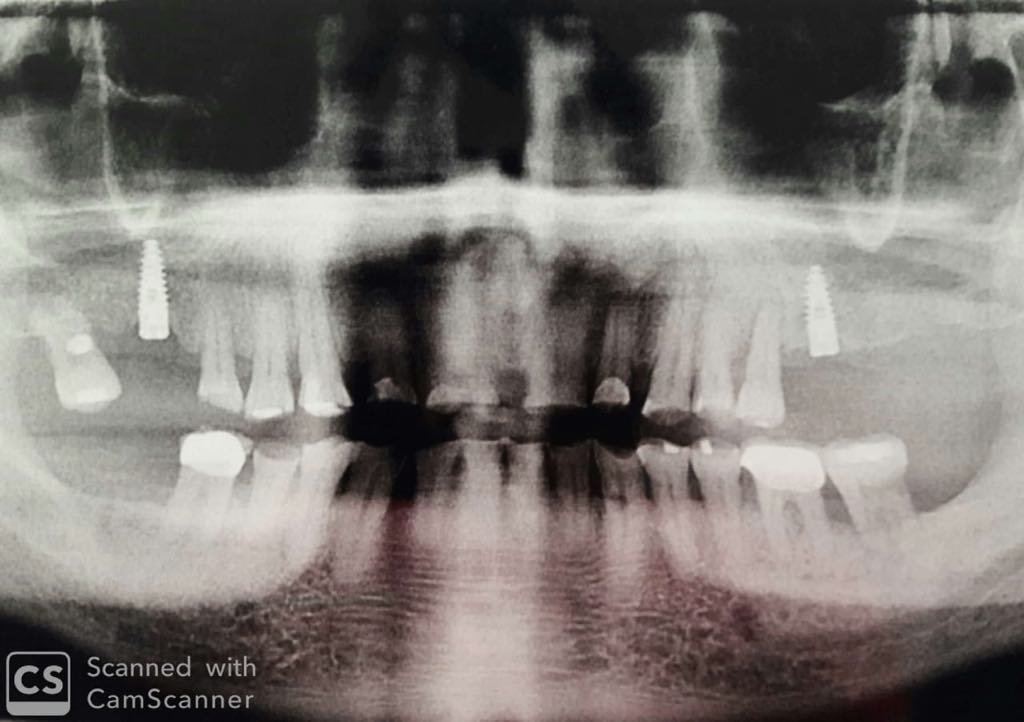

Mujer de 70 años que acude para cambiar corona sobre implante del 3.5 y n o sé que implante es

Paciente acude con este implante que se lo han colocado en otra consulta y me gustaría descubrir cuál es para añadirlo a su historia clínica Gracias de antemano.